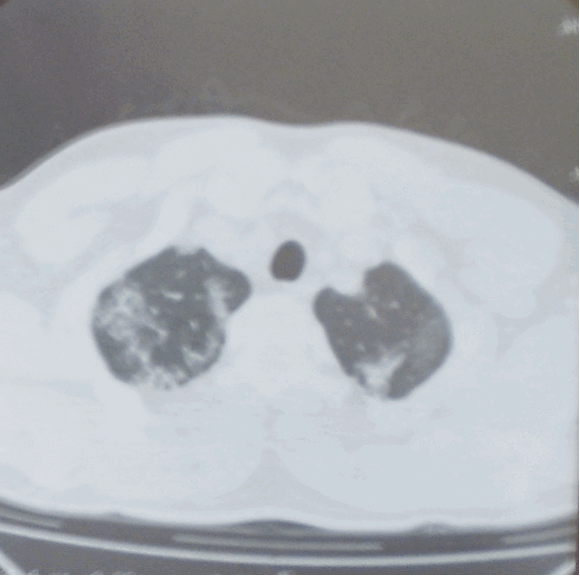

Компьютерная томография органов грудной полости: на серии компьютерных томограмм получены изображения легких и средостения в аксиальной плоскости на уровне вдоха по стандартному протоколу. Легкие обычных размеров и формы, с дополнительной долей непарной вены в правом легком. Легочный рисунок резко деформирован по мелко- и среднепетлистому типу в прикорневых отделах с обеих сторон. Также отмечаются участки и зоны деформации легочного рисунка по мелко- и среднепетлистому типу и по типу «матового стекла» в плащевых отделах легких с обеих сторон – симптом «географической карты». Во всех отделах определяются множественные плевральные сращения. Корни легких структурны, с наличием множественных бронхопульмональных лимфатических узлов (0,2-0,5 см в диаметре) в структуре. Стенки трахеи и бронхов умеренно уплотнены, с наличием мелких бронхоэктазов в задне-базальных отделах слева. Сердце умеренно увеличено в размерах, преимущественно за счет левых отделов. Жидкости в плевральных полостях не обнаружено (рис. 2).

Рисунок 2а. Компьютерная томограмма органов грудной клетки: изменения легочного рисунка по типу «матового стекла». Множественные плевральные сращения

- нетипичная для АП локализация поражения: по данным КТ ОГК отмечается поражение не только задне-базальных, но и верхних отделов легких (рис 2). Помимо этого, визуализируется поражение плевры в виде множественных плевральных сращений, что не характерно для АП.